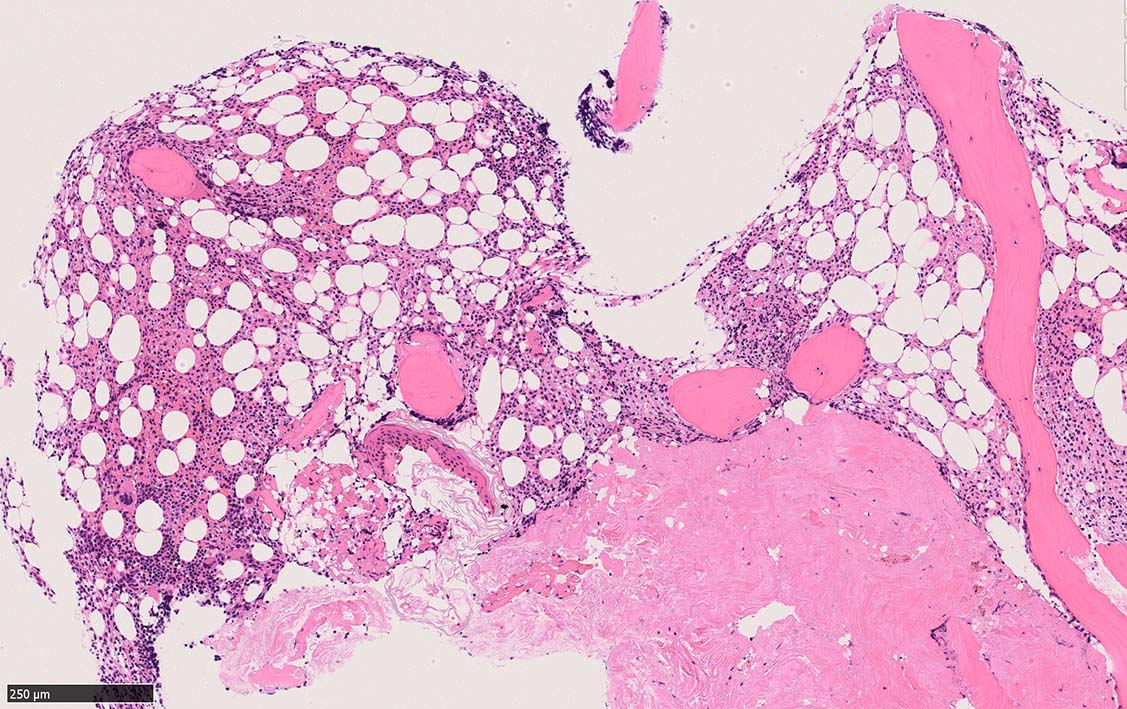

骨髄生検

bone marrow trephine biopsy: dry tapのため骨髄生検が行われる. cellularityは40-80%とhypercellular marrow. 流れのある細胞配列は線維化を疑わせる.

ASD-G 低倍率所見では赤芽球血島は幼若赤芽球の集簇巣が散在する, 顆粒球系細胞(ASDに赤く染色される)は減少,granulopoietic hypoplasiaを呈する.疎な集簇を示すmast cellsの増加がある.

ASD-G陰性の細胞がびまん性に増加しているように見える.